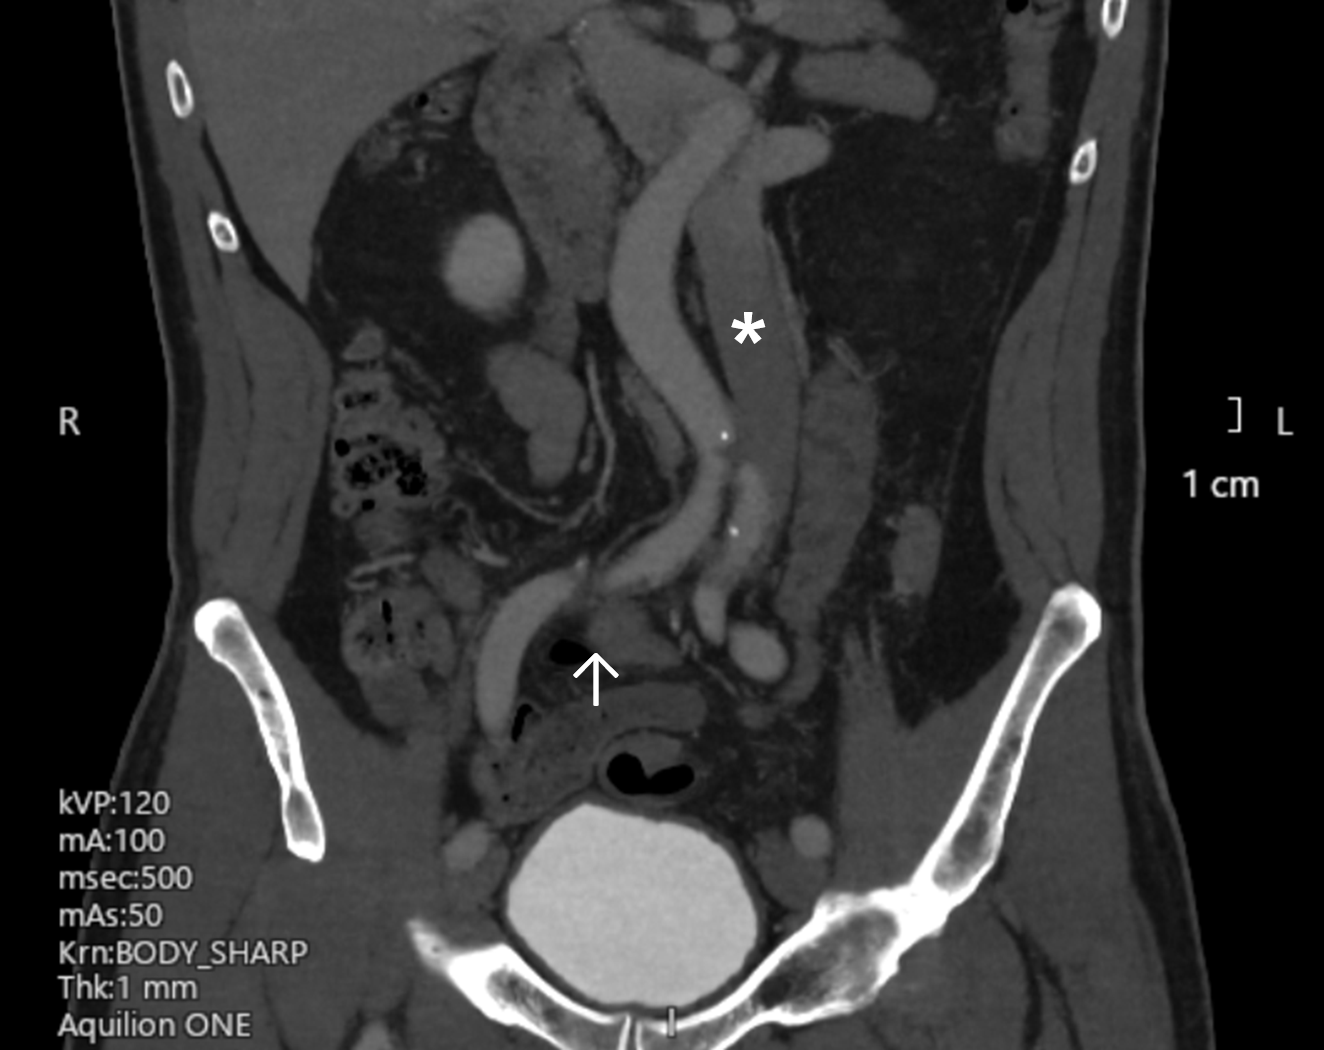

A computed tomography (CT) venogram of the inferior vena cava (IVC) and iliac and femoral veins was arranged. The scan showed a left-sided IVC, which “crossed over” to the right side at the renal vein level (Figure 2). The apparent filling defect was attributable to external compression of the right common iliac vein by the left iliac artery as it crossed to the left side (Figure 3).

Figure 2. (A-C) Three consecutive cuts of coronal plane images (anterior to posterior) from the patient’s computed tomography venogram. The left-sided inferior vena cava is marked with an asterisk. (B) The right iliac vein appeared to be compressed by the left iliac artery (arrow), which may explain the intraprocedural finding.